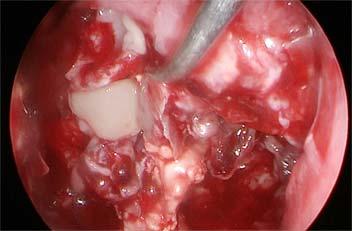

Once Mucormycosis was confirmed, within 72 hours, surgery was performed as well (Fig 2). Post surgery, either Amphotericin B therapy was instituted if it was available and if it was not available then either orally Posaconazole (200 mg q8h) was administered or Isavuconazole at a loading dose of 372 mg orally every 8 hours and maintenance dose of 372mg orally once a day. Inj Amphotericin B was administered at 35 mg/kg. Daily renal function tests had to be performed due to possible nephrotoxicity of Amphoterecin B. Those who could afford, liposomal Amphotericin B injections were given which had lesser renal complications. Alteration in dosage was adjusted according to renal tolerance. Amphotericin B was not available in private clinic/hospitals but only available in government hospitals. Those who were ready to get

Fig 2 — Collage representing resection with debridement of the maxillary lesion and lastly providing an obturator